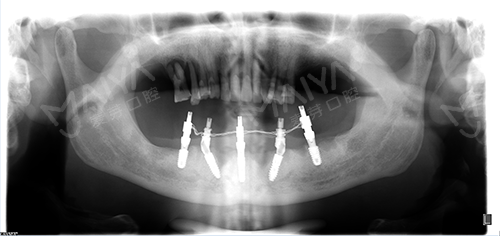

老李种植前全景片检查

种植5颗牙后口腔全景片

经过前期的牙周清洁、治疗后,根据李老口内实际情况,为达到更好的增加负重、增强咀嚼能力效果,麦芽口腔种植医师团队对ALL-ON-4种植技术进行升级和改造,为其量身定制了"ALL-ON-5"种植方案,治疗后总共恢复24颗牙齿。